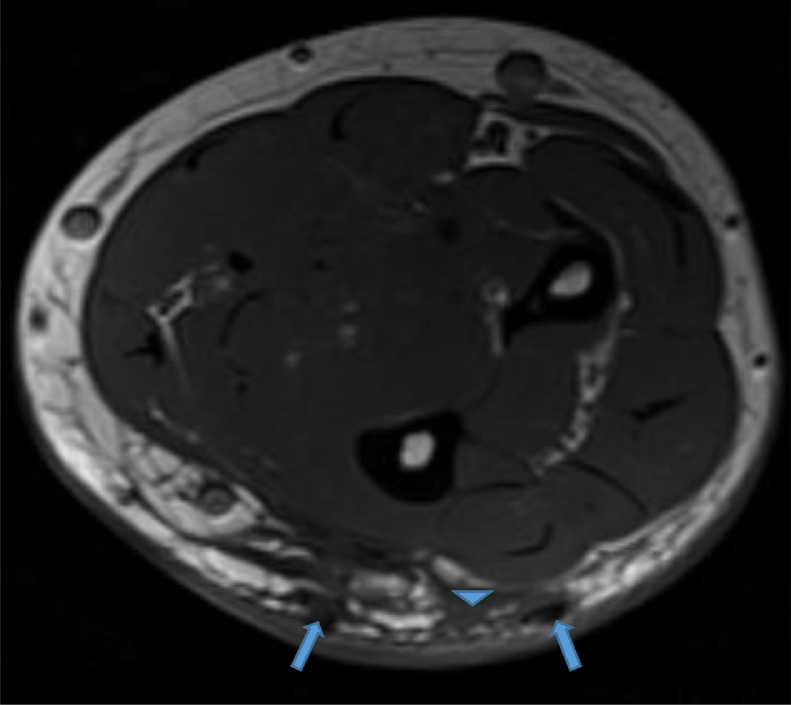

Fig. 2.

Axial proton density (PD) fat saturation image reveals low signal intensity foci (blue arrows) surrounded by high signal intensity fluid infiltrating the subcutaneous fat (blue arrowhead). Color version available online